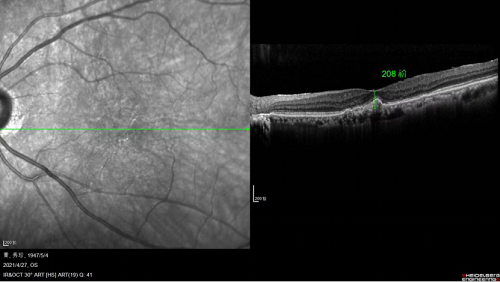

注藥手術(shù)前,黃斑水腫嚴(yán)重

完成一個療程(三針)治療后

黃斑水腫消退,黃斑厚度大大降低